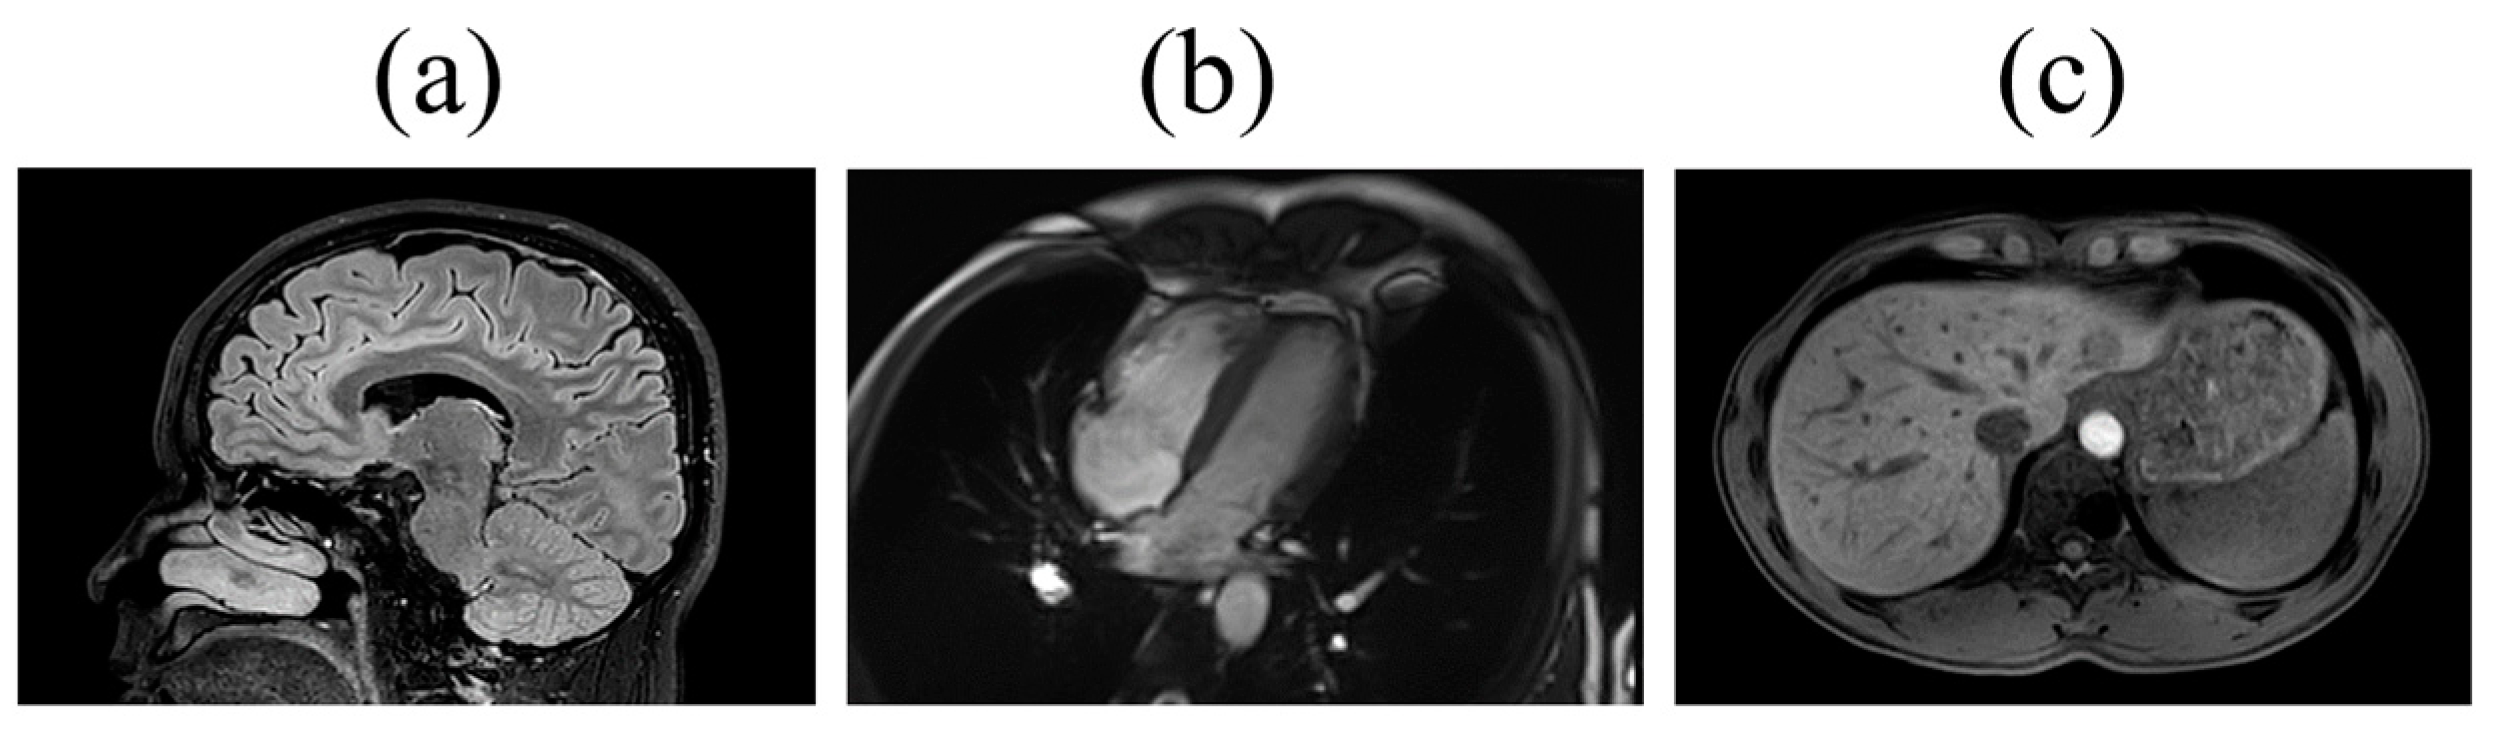

| Brain | volume of grey matter | 25782–25920, 24360–24409 | [16] |

| Heart | cardiac and aortic structure and function | 24100–24181 | [19] |

| Liver | volume/fat fraction/iron/ corrected T1 | 21080, 21088, 21089, 40060, 40061, 40062 | [17,18] |